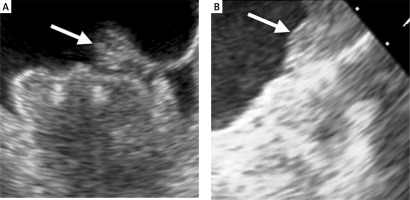

DRT is one of the most concerning complications after successful Watchman device implantation that can be detected by TEE (Figure 4) or CT. In the PROTECT-AF trial the rate of DRT was 4.2% [17]. However, in 2018 Dukkipati et al. published cumulative data regarding DRT incidence in PROTECT AF, PREVAIL, and their continuous access registries [43]. After a mean follow-up time of 4.1 years, the rate of DRT was 3.74%. The analysis of patients with DRT revealed that they were at higher thromboembolic risk assessed with the CHA2DS2-VASc score, were more likely in permanent atrial fibrillation, had a history of TIA or stroke, larger LAA, and had lower ejection fraction (EF). The risk of stroke or systemic embolism was 3.55-fold higher in patients with DRT. In the EWOLUTION registry, at 2-year follow-up DRT was observed in 34 (4.1%) cases among 835 patients with imaging of the LAA after a median time of 54 days (IQR: 41–111 days) [44]. Thirty-one incidents of DRT were observed at the first follow-up imaging usually within 90 days after the procedure. DRT occurred irrespective of the type of the post-LAAC antithrombotic regimen. Patients with DRT more often had non-paroxysmal AF, evidence of spontaneous echo contrast, and a larger ostium diameter of the LAA [45]. Overall, no significant differences in rate of thromboembolic events were observed in patients with or without DRT (1.7 vs. 2.2%/year, p = 0.8). In a prospective registry with the second-generation Watchman FLX device, at 1 year DRT was detected in 7 (1.7%) patients with 4 cases discovered during scheduled follow-up visits [28]. In the real-world registry of Watchman FLX, DRT was observed in 2.4% of cases through 1 year of follow-up and all were detected during routine imaging [30].

Figure 4

Device-related thrombus on Watchman 2.5 device. The arrow indicates a thrombus on the surface of the implanted device